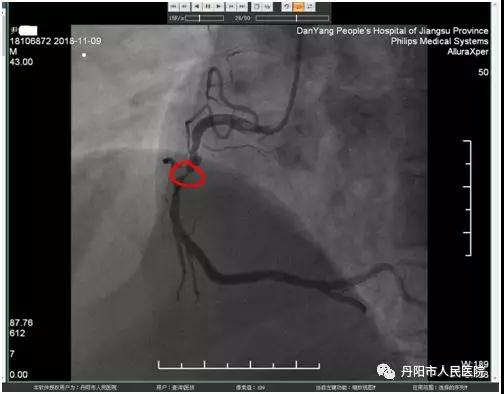

(右冠中段次全闭塞,红圈中为血管闭塞处)